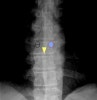

X-ray : Coarse, vertical striation

-

CT : Polka dot appearance